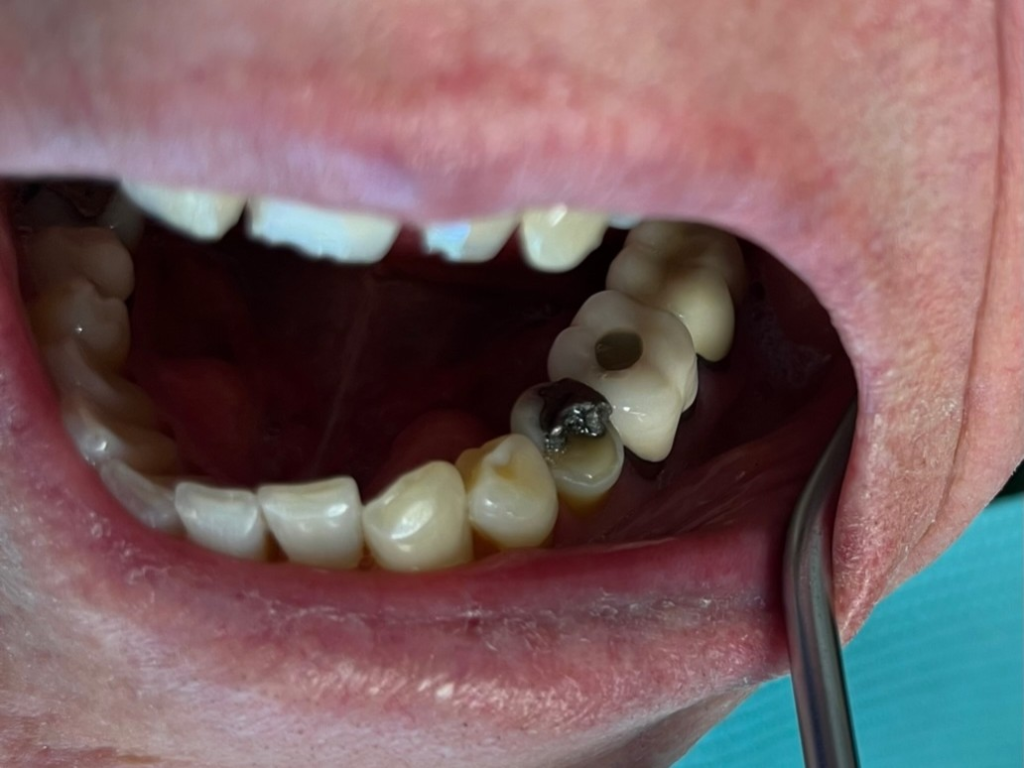

4

Posterior DentXpinTM repair.